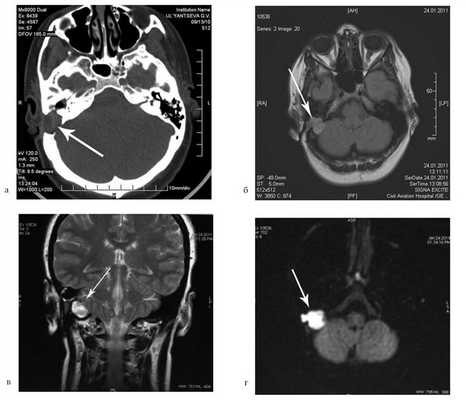

Больной А., 44 лет, обратился с жалобами на периодические (2 раза в год) гноетечения из правого уха. Ранее пациенту неоднократно предлагалось оперативное вмешательство.

При отомикроскопии определяется утолщение барабанной перепонки, перфорация не визуализируется, признаков холестеатомы нет.

На КТ правой височной кости определяется затемнение в области аттика и антрума, цепь слуховых косточек сохранена (рис. 3, а). Рисунок 3. КТ и МРТ височных костей больного А. с адгезивным средним отитом справа, фиброзной облитерацией аттика. а — КТ; б — МРТ основания черепа в режиме Т1; в — в режиме Т2; г — в режиме non-EPI DWI.

Пациенту выполнена МРТ основания черепа по описанной методике (рис. 3, б—г).

В режиме Т1 и Т2 справа определяется очаг с высокой интенсивностью сигнала, тогда как в режиме non-EPI DWI патологических образований не выявлено. Диагноз: адгезивный средний отит справа, фиброзная облитерация аттика.

В связи с отсутствием данных о холестеатоме операция не производилась, выявленные изменения расценены как фиброзные изменения, оторея была обусловлена периодическим возникновением наружного отита. Больной получал консервативное лечение.